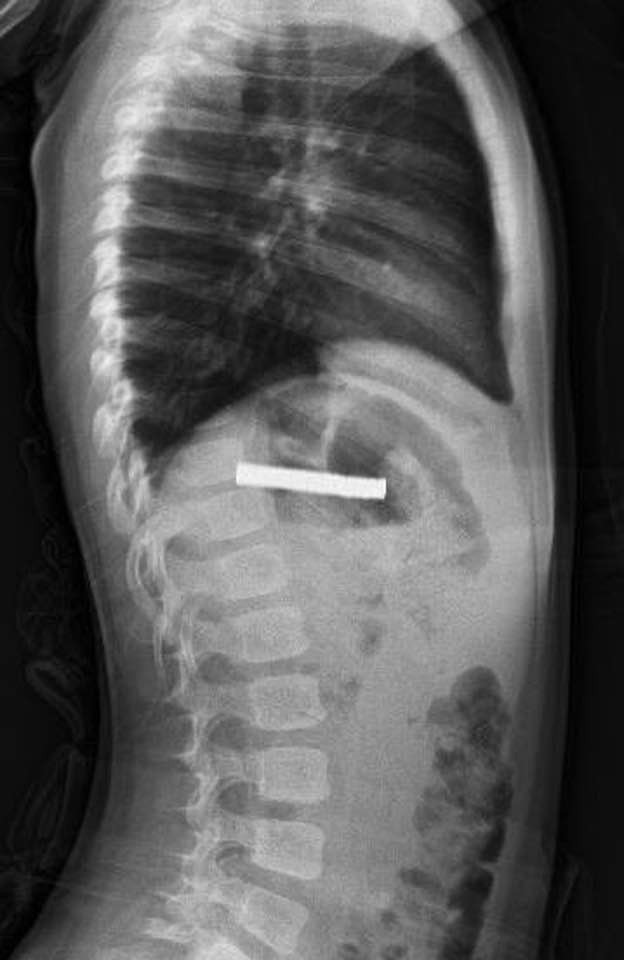

Elazığ’da doktorlar, 3 yaşındaki bir çocuğun yuttuğu 19 mıknatısı başarılı bir operasyonla çıkardı.

Edinilen bilgilere göre, Erzurum’da yaşayan çocuk, evde oynadığı sırada 19 adet mıknatısı yuttu. Ailesinin durumu fark etmesi üzerine hastaneye başvuruldu ve çocuk Elazığ Fırat Üniversitesi Hastanesine sevk edildi.

Fırat Üniversitesi Çocuk Gastroenteroloji Hepatoloji ve Beslenme Bilim Dalı Başkanı Prof. Dr. Yaşar Doğan tarafından gerçekleştirilen endoskopik operasyonla mıknatıslar çocuğun yemek borusundan çıkarıldı.

Uzun süre yemek borusunda takılı kalan mıknatısların, yemek borusu ve mide girişinde zedelenmelere yol açtığı öğrenildi.